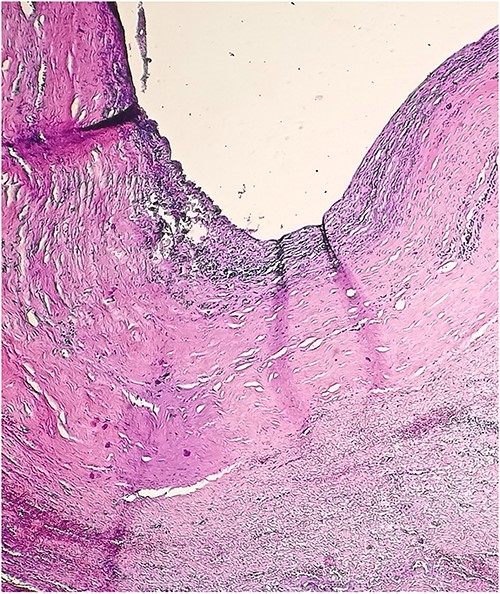

A 46-year-old male presented with mild abdominal pain for the last 2 months. The pain was generalized, recurrent and did not relieve on medication. The patient showed intermittent claudication in his right leg. He presented with a similar complaint five years ago; abdominal pain and urinary urgency and hesitancy, which led to a diagnosis of a simple abdominal cyst. Past medical history was insignificant. Surgical history included retroperitoneal cystectomy, herniorrhaphy and a cleft palate repair. Patient had no other complaints and was not on any medications. He was a smoker with a 22 pack-year smoking history. His temperature was normal, and there was no history of weight loss or loss of appetite or change in bowel movement. On physical examination, the abdomen was soft and non-tender without distention. There was a palpable mass in his right flank. Vital signs and blood tests were within normal limits. Abdominal ultrasound (US) showed a large fluid-filled cystic lesion (Fig. 1a). Subsequent computerized tomography (CT) of the abdomen showed a large, well-defined, clear fluid-filled cyst measuring 17 × 11 × 10 cm, located in the retroperitoneum abutting the lower half of the right kidney, extending to the pelvis and compressing the inferior vena cava (Fig. 1b). Patient was cleared for surgery. Surgical exploration showed several adhesions surrounding the cyst. The cyst was partially isolated from the right ureter and iliac vein and artery (Fig. 2a and b), then surgical excision of 90% of the cyst was performed (Fig. 3). Histopathological report found the cystic wall composed of fibrous connective tissue and lined by one layer of flat cells, with mild lymphocytic infiltrate and congested blood vessels confirming the diagnosis of a chylolymphatic cyst (Fig. 4). On a 1-year follow-up, the patient appears to be recovered and in good health with no recurrence.

a. An US image showing a large cystic mass in the right abdomen. b. A CT scan of the abdomen showing a cystic mass of 17 × 11 × 10 cm with a fat-fluid level.